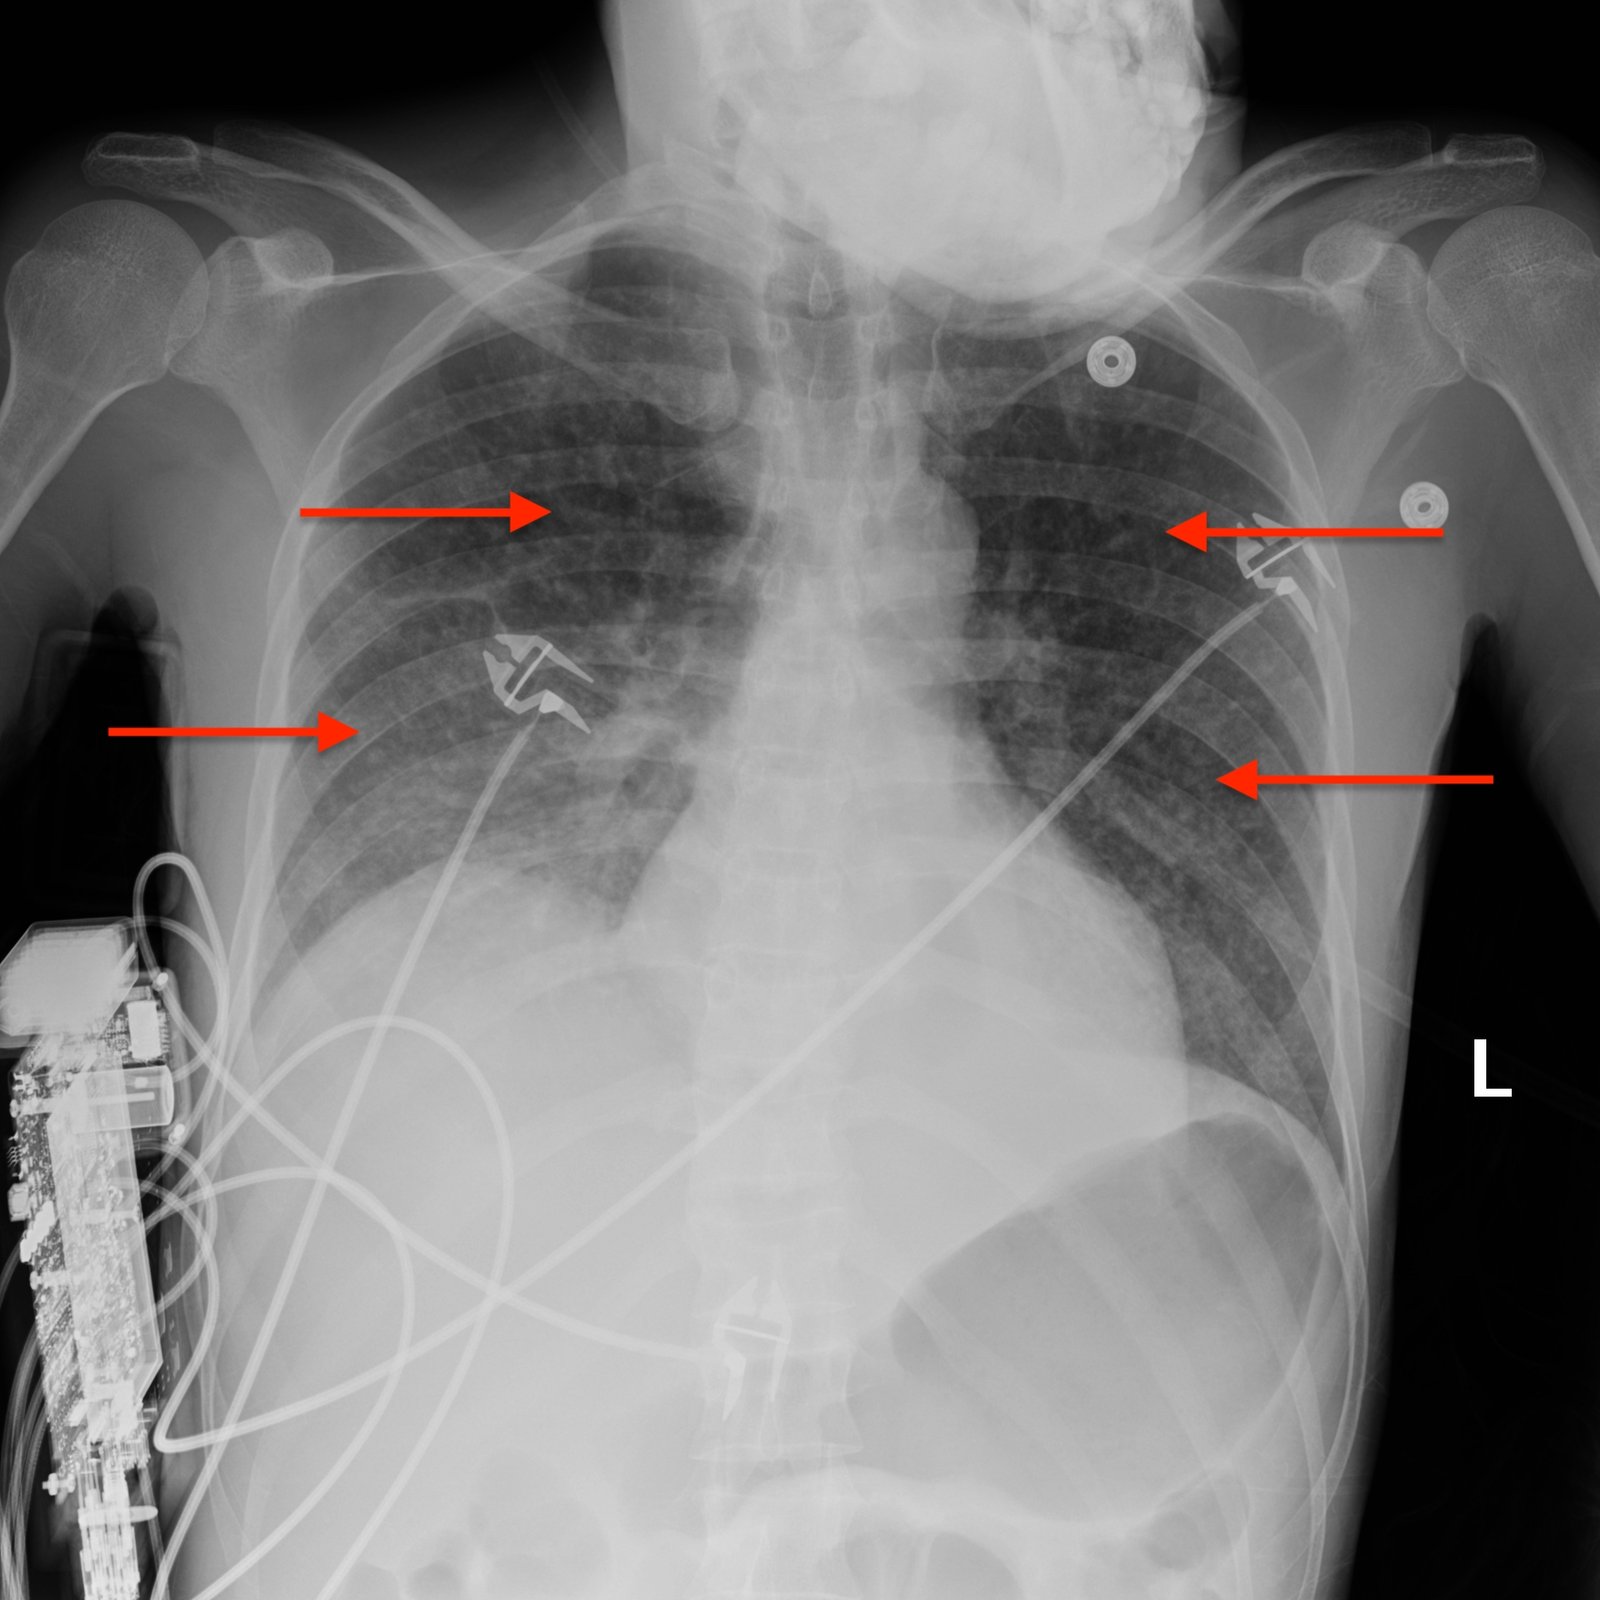

Miliary TB, Portable X-Ray, Annotated. JETem 2020

A Case Report on Miliary Tuberculosis in Acute Immune Reconstitution Inflammatory Syndrome